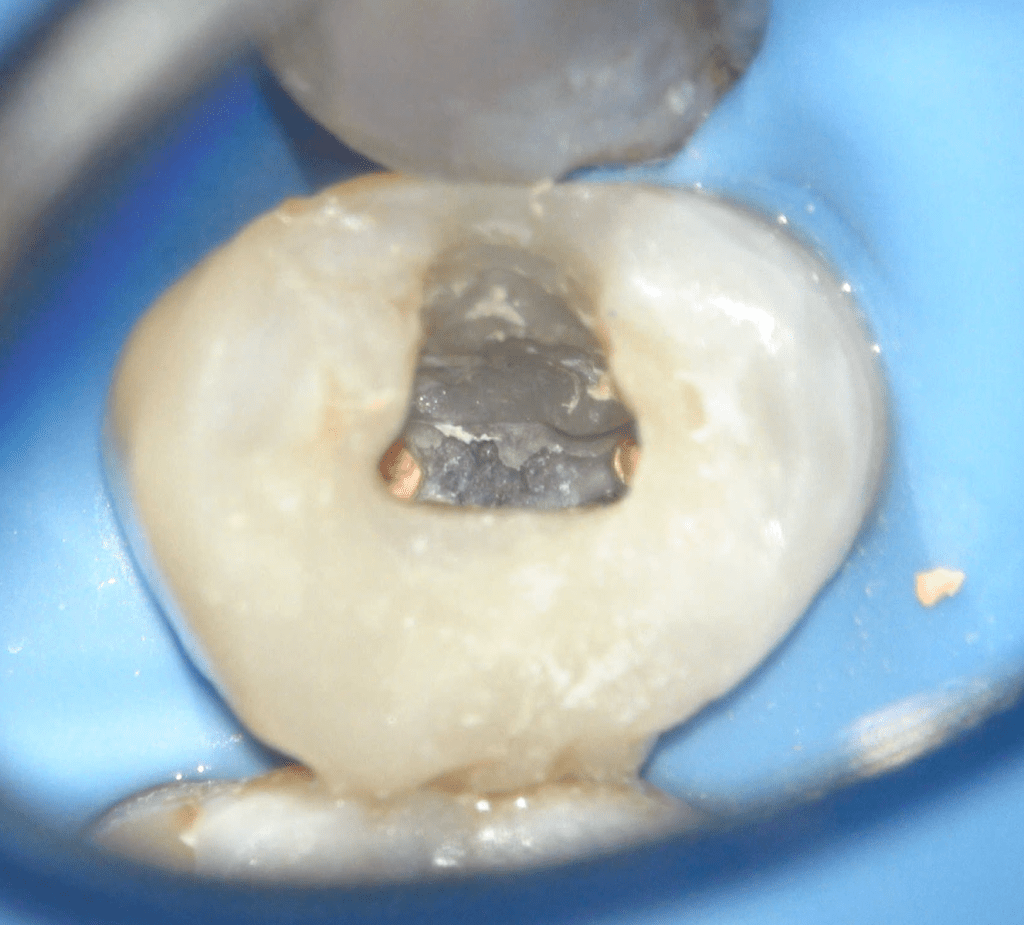

Reconstrucción preendodóntica

Reco preendo, 2o Molar superior